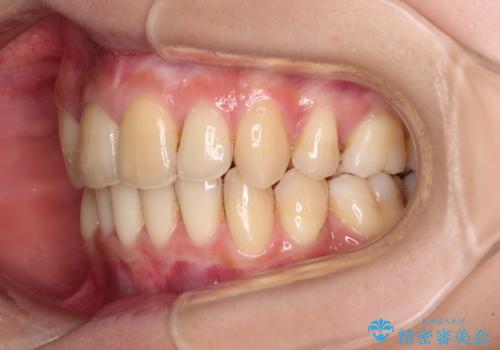

出っ歯を治したい ワイヤー装置による抜歯矯正

- 上下の出っ歯を気にして来院された患者様です。

口元を積極的に引っ込めるために、上下左右の小臼歯を4本抜歯することとしました。

右上前から2番目の歯が欠損しているため、①矯正治療により欠損部にスペースを作りインプラント補綴を行って前歯を左右対称に揃える、②左右非対称となるが、欠損補綴を行わずに排列する、のいずれかとなりますが、患者様と相談の上②にて矯正治療を行うこととしました。

変則的な歯列であったため、奥歯がしっかりと咬み合うのか、前歯はしっかりと排列できるのかと不安ではありましたが、結果としてはきれいに整った歯列にて終了することができました。